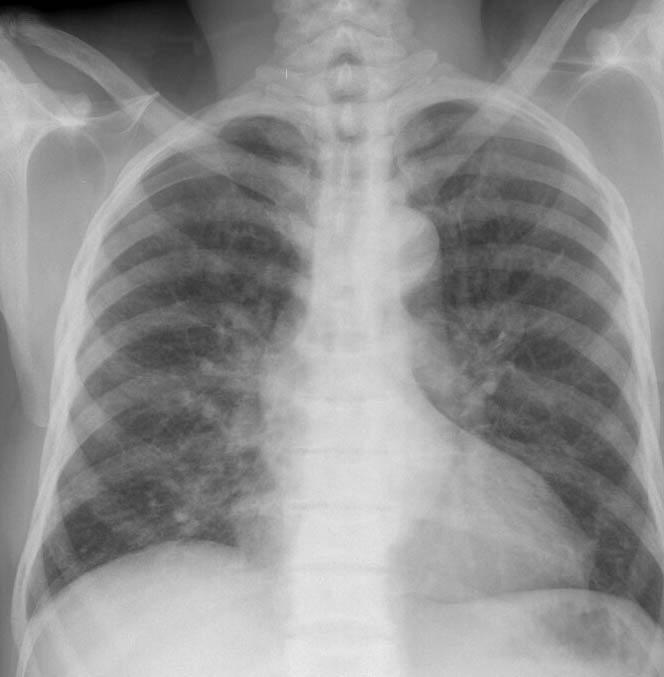

Gallery Congenital Sickle Cell 1 PA

Sickle Cell 1 PA